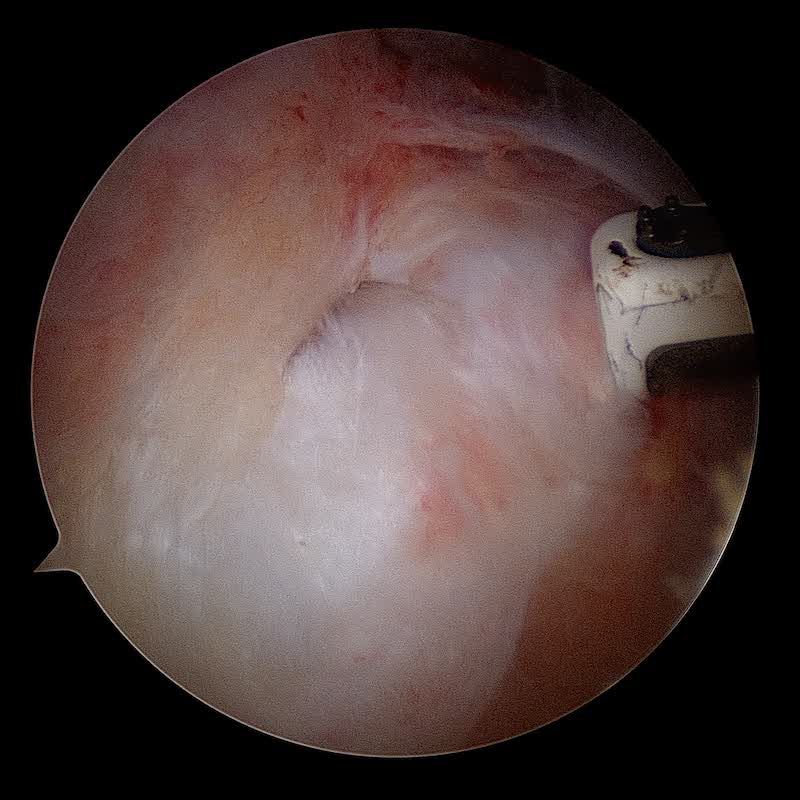

La réparation du (ou des) tendon(s) est réalisée sous arthroscopie grace à des ancres miniaturisées sur lesquelles sont fixés des fils très résistants qui permettent de réinsérer les tendons sur l'os pour permettre leur cicatrisation. Une acromioplastie et un geste sur le biceps (ténotomie ou ténodèse) sont le plus souvent associés.

La chirurgie de la coiffe des rotateurs est une chirurgie spécialisée qui est aujourd’hui réalisée dans 99% des cas sous arthroscopie (avec une caméra sous vidéochirurgie). La réparation de la coiffe des rotateurs sous arthroscopie est un acte chirurgical exigeant un chirurgien entrainé; la réparation peut nécessiter d'utiliser différentes techniques selon la forme de la rupture, sa taille et la qualité des tendons.

Technique de réparation de la coiffe des rotateurs sous arthroscopie:

Cette vidéo vous montre une procédure classique de réparation de la coiffe des rotateurs sous arthroscopie.Il s'agit d'images de synthèse. La technique utilisée est un double rang d'ancres. Les ancres médiales sont placées au ras du cartilage. Les ancres latérales qui servent à plaquer la coiffe sur le footprint sont placées à la face externe de l'Humérus. Les ancres sont montées sur des sutures non résorbables composées de fils et de bandelettes.

La rupture tendineuse est visualisée dans l'espace bursal sous la forme d'un "trou" dans le tendon. Les fibres tendineuses parthologiques sont réséquées afin de ne garder que du tendon sain. C'est ce tendon qui va être ensuite réinséré sur l'os.